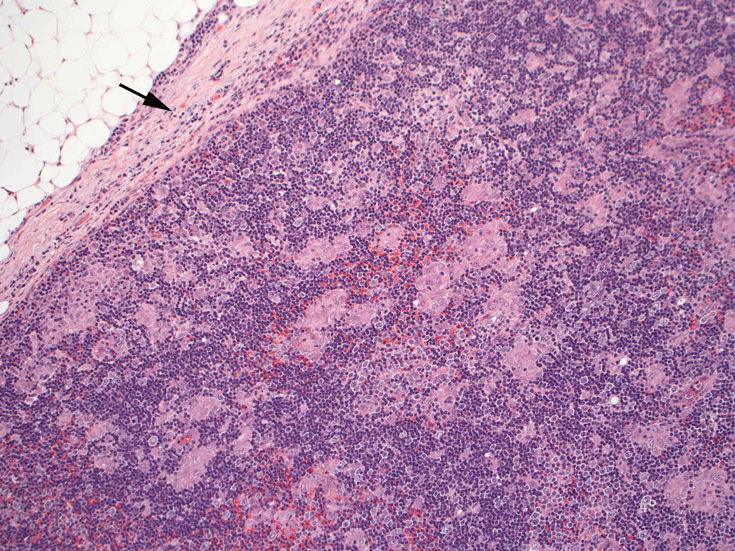

通常傍濾胞領域に小型, 不整形の類上皮細胞肉芽腫が多数形成されている。この症例では慢性炎症を伴い線維性に肥厚した皮膜直下にも多くの肉芽腫病変が散在する。Piringer型リンパ節炎と呼ばれる。

皮質から傍皮質に肉芽腫が散在大小不整な肉芽腫looseな肉芽腫皮膜下にも肉芽腫あり